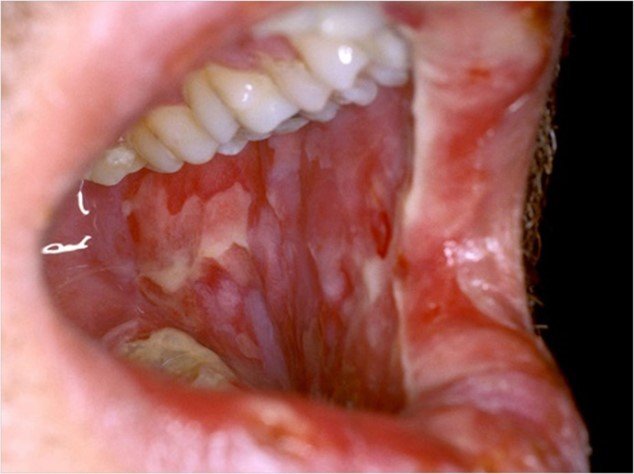

Oral mucositis is a severely debilitating condition characterized by erythema, edema, and ulcerations of the oral mucosa.

Evaluating for oral mucositis is dependent upon clinical history and physical exam findings. Laboratory and radiography are not as helpful. If ulcers are present on the hard palate, attached gingiva, or tongue dorsum, cultures should be obtained to rule out viral or fungal etiology.